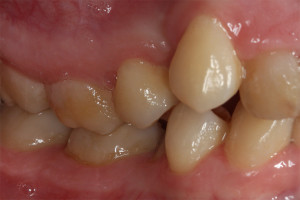

Młoda pacjentka zgłosiła się do naszego gabinetu celem wykonania kompleksowego leczenia zachowawczo-ortodontycznego. Oprócz problemów natury ortodontycznej stwierdzono złą higienę jamy ustnej oraz liczne potrzeby leczenia zachowawczo-endodontycznego. Po wnikliwej analizie telerentgenowskiej oraz analizie modeli zadecydowano o ekstrakcji 2 zębów w łuku dolnym (kła po stronie lewej oraz pierwszego przedtrzonowca po stronie prawej). Plan leczenia obejmował ponadto zamknięcie łuku po brakujących zębach w łuku górnym. Leczenie aktywne trwało 2 lata i 8 miesięcy. W czasie jego trwania pacjentka była regularnie poddawana zabiegom higieny profesjonalnej celem eliminacji zapaleń przyzębia brzeżnego. Po leczeniu aktywnym zastosowano leczenie retencyjne w postaci retainera stałego w żuchwie oraz szyny retencyjnej w łuku górnym.